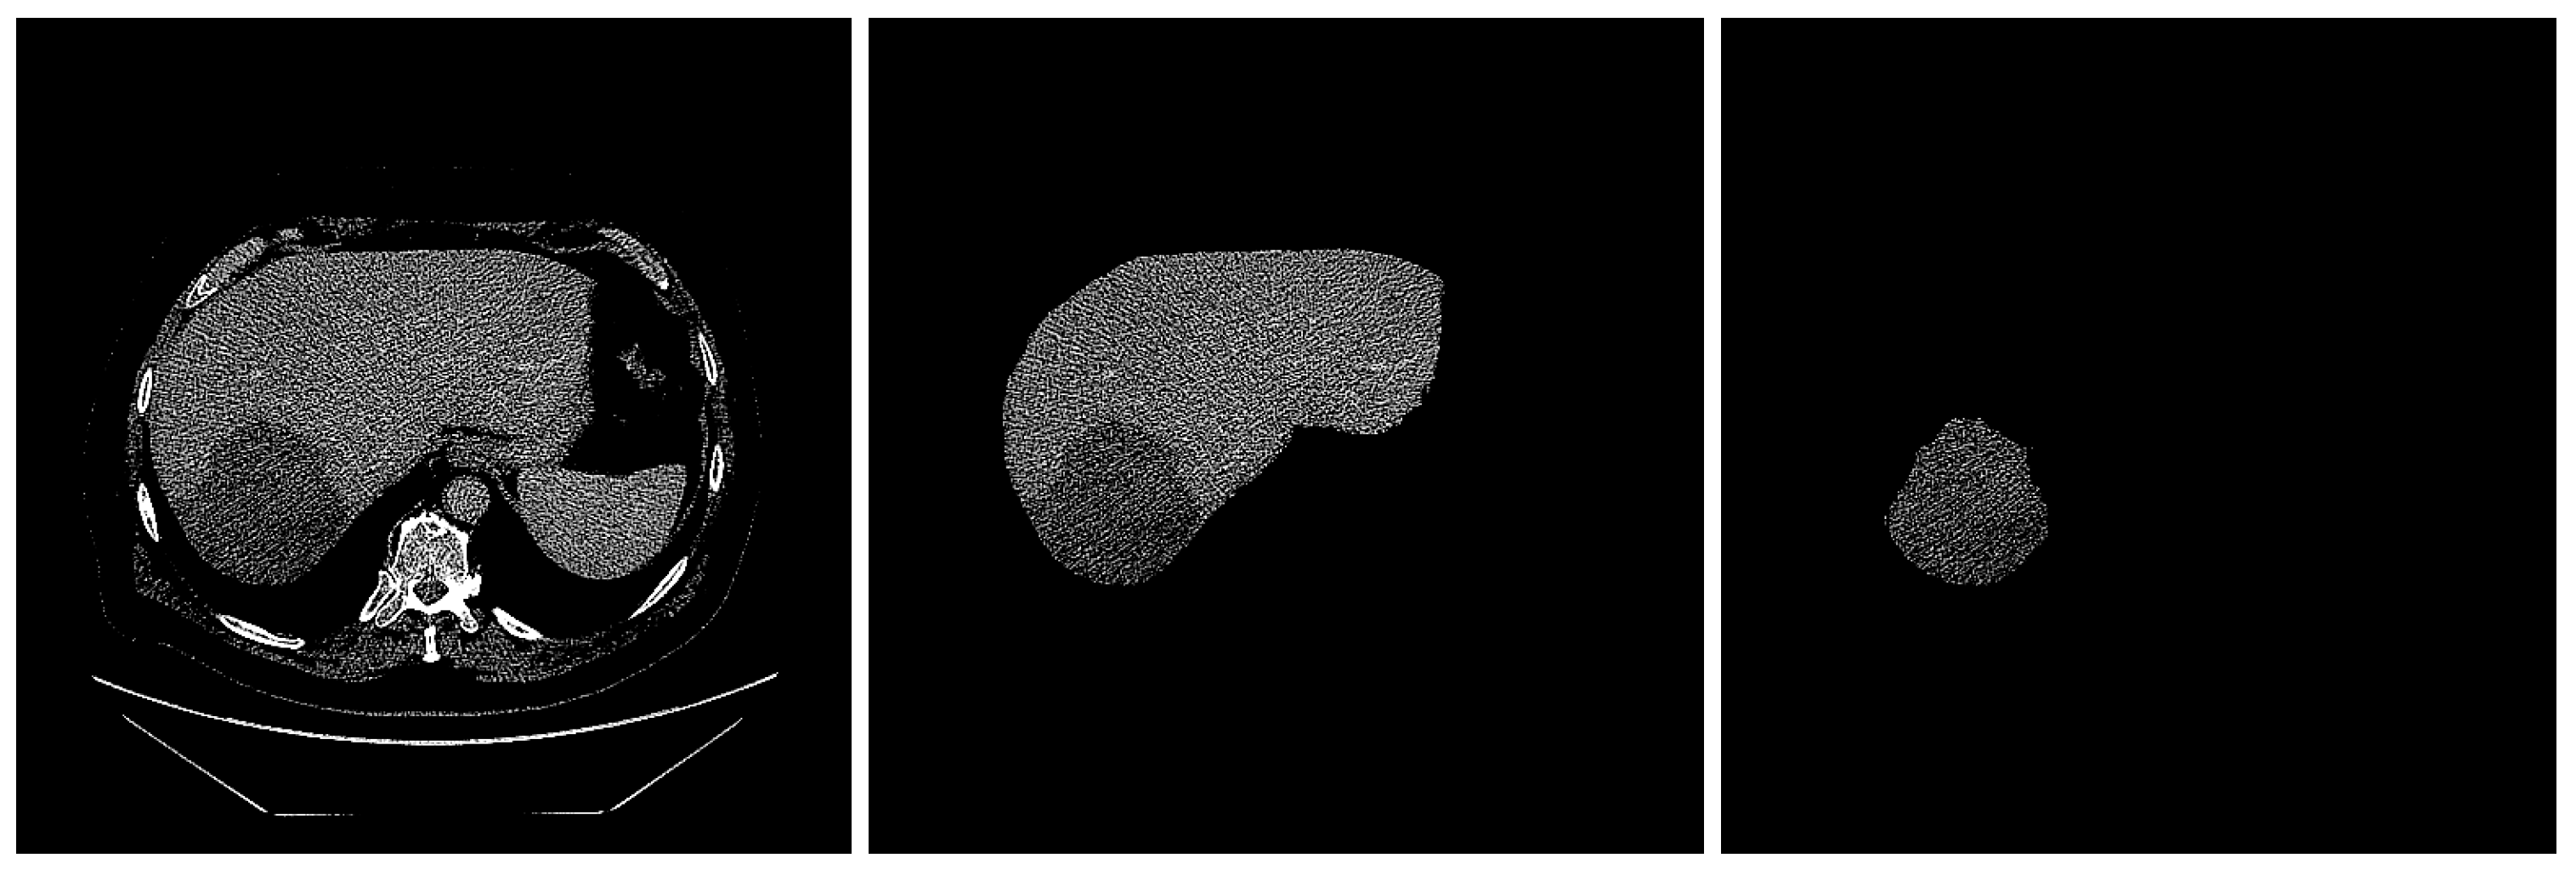

2.3. ROI Segmentation